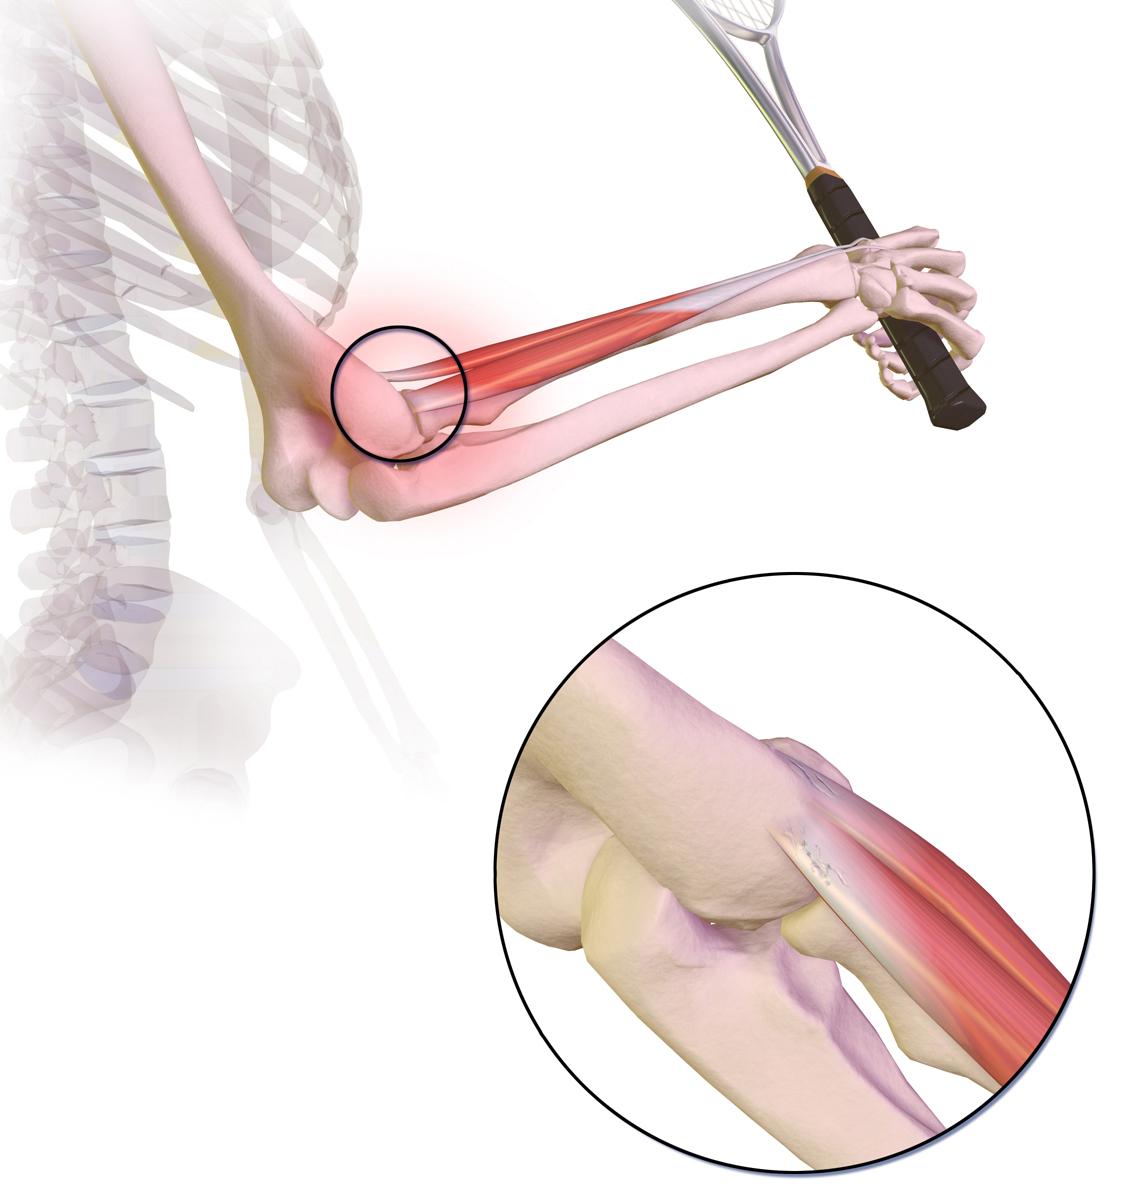

This picture shows where the pain is felt, on the outside of the elbow, in tennis elbow:

Tennis elbow

By BruceBlaus, CC BY-SA 4.0, via Wikimedia Commons